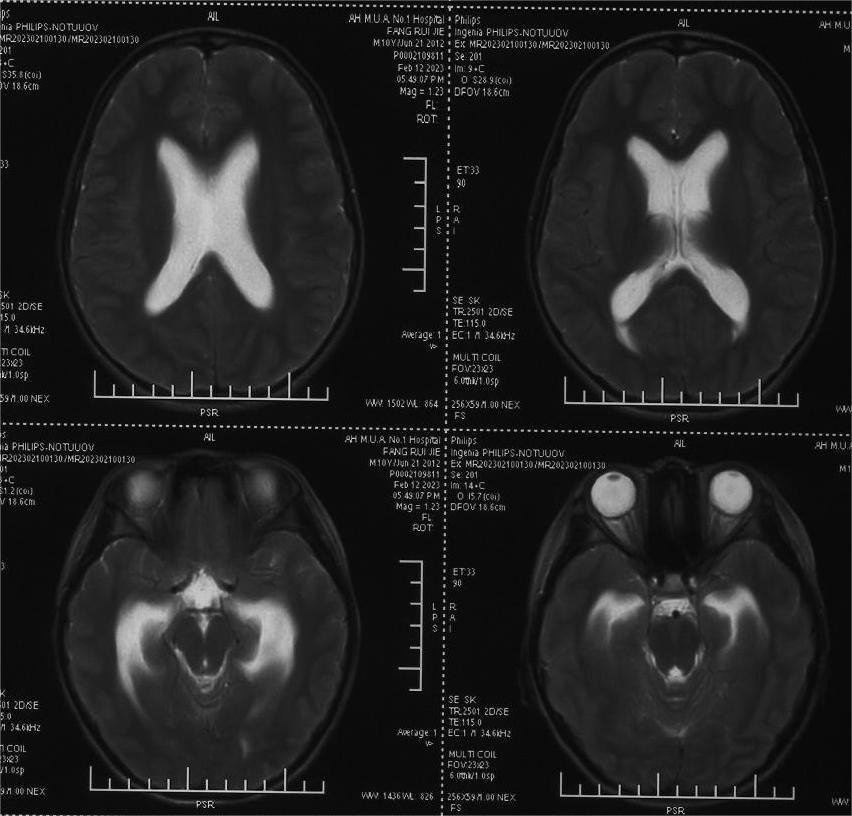

患儿方x,10岁9月,因“头痛、呕吐1月,外院行三脑室底造瘘术后2周”入院。患儿1月前无明显诱因下出现头痛,严重时伴有喷射性呕吐,就诊当地医院,检查发现松果体区占位、脑积水,行三脑室底造瘘术(图1)。术后患者头痛呕吐症状明显缓解,但新出现间断癫痫大发作,予以丙戊酸钠+氯硝西泮抗癫痫抗癫痫治疗,控制满意。就诊我院,神经系统查体未见明显异常。脑MRI检查提示松果体区占位(图 2A-C)。

图1,术前脑室稍扩大